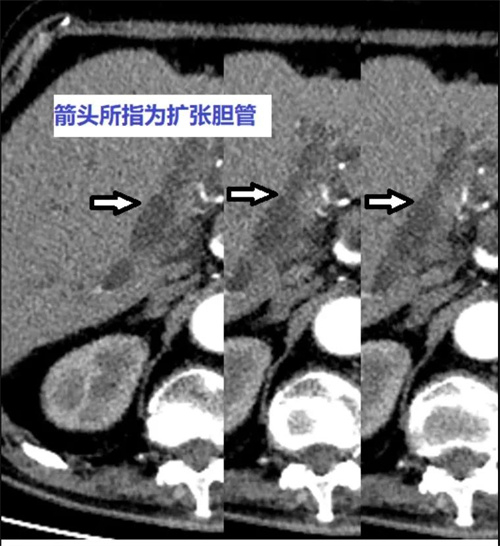

現(xiàn)年85歲的吳老太(化名)患有高血壓、心臟病、冠心病等多種疾病,身體狀況一直不好。近來她出現(xiàn)腹部持續(xù)性疼痛、嘔吐等癥狀,被家人緊急送往北京大學(xué)人民醫(yī)院青島醫(yī)院(青島婦兒醫(yī)院城陽院區(qū))急診救治。經(jīng)過檢查,吳老太被診斷患有膽總管結(jié)石伴梗阻性化膿性膽管炎,需要轉(zhuǎn)入肝膽外科病房治療,后續(xù)通過手術(shù)取出結(jié)石。

入院后,吳老太淤積的膽汁在膽管內(nèi)繼發(fā)感染,一天內(nèi)數(shù)次高燒、寒戰(zhàn),血壓降至80/50mmHg以下,甚至出現(xiàn)多器官衰竭。因為老人病情危重,無法耐受常規(guī)手術(shù)創(chuàng)傷,如何以損傷最小、風險最低的治療方案疏通膽道梗阻成為目前的燃眉之急。

肝膽外科在控制感染性休克的同時,立即組織重癥監(jiān)護室(ICU)、消化、介入、麻醉、導(dǎo)管手術(shù)室等相關(guān)學(xué)科會診。專家們經(jīng)過討論,為吳老太制定了治療方案:采用創(chuàng)傷風險較小的經(jīng)皮肝穿刺膽道引流術(shù)(PTCD)解除膽道梗阻,保護肝臟功能,為下一步手術(shù)治療創(chuàng)造有利條件。

北京大學(xué)人民醫(yī)院青島醫(yī)院(青島婦兒醫(yī)院城陽院區(qū))專家介紹:經(jīng)皮肝穿刺膽道引流術(shù)(PTCD)是在影像技術(shù)下經(jīng)皮經(jīng)肝在膽道內(nèi)放置導(dǎo)管的技術(shù),通過內(nèi)引流和外引流的方式引流膽汁。該技術(shù)主要適用于治療不宜手術(shù)切除的危重急性膽囊炎、膽管炎等患者和老年患者,對低位膽道梗阻患者也可起到膽道引流的作用。因創(chuàng)傷小、時間短、并發(fā)癥少等優(yōu)點,成為解除膽道梗阻的重要治療方法。(本網(wǎng)記者)